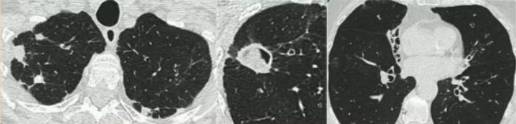

慢性空洞性肺曲霉病(CCPA):最常见,单发或多发的肺空洞(薄壁或厚壁),空洞内可包含一个或多个曲菌球或不规则的腔内物质,具有曲霉菌血清学和微生物学依据,并有明显肺部和全身症状,至少3个多月的视察有放射影像学进展(新发空洞,空洞外周浸润增加及纤维增生增加)。

慢性纤维化性肺曲霉病(CFPA):常因未经规范治疗的CCPA发展而来,至少有两个肺叶的严重纤维化破坏,伴肺功能丧失。而单发空洞伴一个肺叶的严重纤维化性破坏,简称为CCPA影响的肺叶。

亚急性侵袭性肺曲霉病(SAIA):轻度免疫缺陷的侵袭性肺曲霉病患者,发生在1-3个月内,具有可变的影像学特征,包括空洞、结节、有“脓肿形成的进展性实变”。最重要的特征为肺组织发现菌丝,另血液或呼吸液GM试验呈强阳性。